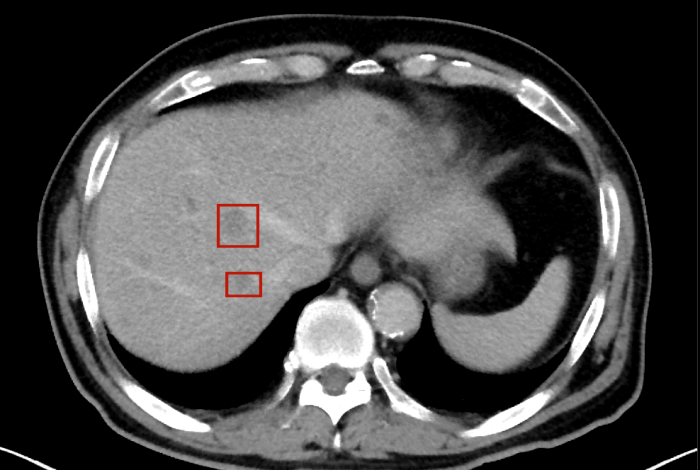

術后,萬秀萍為黃先生做進一步的檢查,腹部磁共振(MRI)檢查顯示:肝臟區(qū)域出現(xiàn)了轉移病灶的陰影。

轉移病灶的陰影